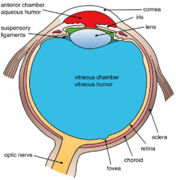

Schematic diagram of the human eye. | |

Structure

The lens is part of the anterior segment of the eye. In front of the lens is the iris, which regulates the amount of light entering into the eye. The lens is suspended in place by the suspensory ligament of the lens, a ring of fibrous tissue that attaches to the lens at its equator[1][2] and connects it to the ciliary body. Posterior to the lens is the vitreous body, which, along with the aqueous humor on the anterior surface, bathes the lens. The lens has an ellipsoid, biconvex shape. The anterior surface is less curved than the posterior. In the adult, the lens is typically circa 10 mm in diameter and has an axial length of about 4 mm, though it is important to note that the size and shape can change due to accommodation and because the lens continues to grow throughout a person's lifetime.[3]

Another view of the eye and the structures of the eye labeled

-